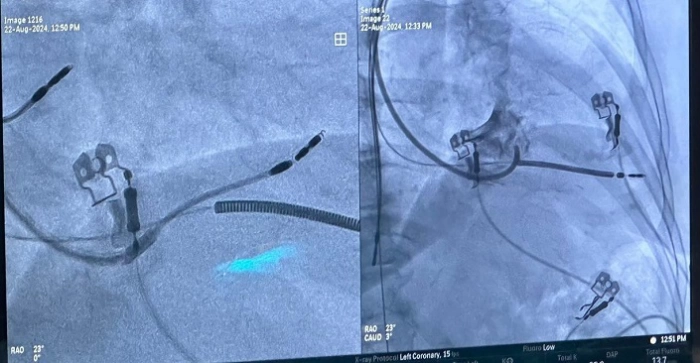

Türkiye'de sadece belirli merkezlerde yapılan ‘Sol Dal Pacing' ameliyatı Fethi Sekin Şehir Hastanesi'nde 3 hastanın ameliyat edilmesiyle başladı. Hastanede görevli Kardiyoloji Uzmanları Dr. Öğretim Üyesi Zeki Çetinkaya ve Uzm. Dr. Mehmet Ali Gelen, aldıkları eğitimin ardından hastanede ‘Sol Dal Pacing' yöntemi ile kapalı pil ameliyatını başarılı bir şekilde gerçekleştirdi. Kalbin içerisindeki çarpıntıların tespit edilmesi ve ardından ablasyon ile teknik tedavi uygulanan ameliyat yöntemi, daha önceden yapılan kalp ameliyatlarının nefes darlığı ve kalp yetmezliği oluşturmasını ortadan kaldırıyor. Başarılı ameliyatların ardından bilgiler veren doktorlar, dünyada yeni uygulanan Türkiye'de ise belirli merkezlerde yapılan ameliyat yöntemi ile Fethi Sekin Şehir Hastanesi'nin bu alanda öncü olacağını belirtti.

Bundan sonra da bu şekilde devam edeceğiz. Bu ameliyatın özelliği kalbin doğal ileti sistemi üzerine pil kablosunu yerleştirdikten sonra kalbin sağ ve sol karıncıklarının uyumlu şekilde çalışmasını sağlıyoruz. Diğer normal taktığımız pillerde ise öncelikle kalbin sağ karıncık kısmı uyarılıyor, sonra sol karıncık kısmı geç uyarılıyordu. Bu şekilde 10 hastanın 2'sinde kalp yetmezliği ve nefes darlığı olabiliyordu. Bu pil yöntemi, dünyada yeni uygulanıyor. Hastalarımız bu ameliyat yöntemi ile daha fayda görmektedir. Özellikle ritim bozukluğu ve nefes darlığı olan hastalarda bu işlemleri başarılı şekilde uygulamaktayız. Bu ameliyat, Ankara, İstanbul ve belirli merkezlerde yapılmaktadır. Burada ise ilk defa yaptık ve başarılı olduk. Katkılarından dolayı Prof. Dr. Uğur Canpolat hocamıza da teşekkür ederiz. Buranın ilerleyen dönemlerde bölge merkezi olma ihtimali de çok yüksek. Bu ameliyatın özelliği doğal ileti sistemi üzerine kablo koyularak kalbin senkron şeklinde yani iki ventürkülün de aynı anda kasılmasını sağlıyoruz. Bu şekilde hastalarda nefes darlığı daha az oluyor. Bu pil yöntemi takıldığında hastalarımız daha konforlu ve nefes darlığı olmayacak şekilde yaşamlarını devam ettirebilirler” dedi.

Kardiyoloji Uzmanı Dr. Mehmet Ali Gelen ise “Normalde kalp yetersizliği ve ritim bozukluğu olan hastalarımızda kalp pili, sık tercih edilen bir yöntemdir. Özellikle dünyada yeni yapılan ve Türkiye'de bazı merkezler de yapılan bu yeni yöntemi bizde Elazığ'a kazandırmak istedik ve 3 hastamızın ameliyatlarını başarılı bir şekilde gerçekleştirdik. Özellikle kalbin ana ileti sistemine pacing yaparak bir pil ablasyonu yapıldı. Bu hastalarda kalp yetersizliğini riskini azaltır ve yaşam konforunu arttırır. Aynı zamanda hastaların ilaç tedavisi yanıtını da arttırabilen bir yöntemdir. Önceden hastalar, bu tarz özellikli işlemleri yaptırmak için Ankara, İstanbul, İzmir ve Bursa gibi şehirlere gitmeleri gerekiyordu fakat biz bu sol dal pacing ameliyatını başarılı bir şekilde yaptık. Bundan sonra bölge ve Elazığ'da ki tüm hastalar, farklı bir şehre gitmeye gerek duymadan Fethi Sekin Şehir Hastanesi'nde ameliyatlarını olabilecekler” ifadelerini kullandı.